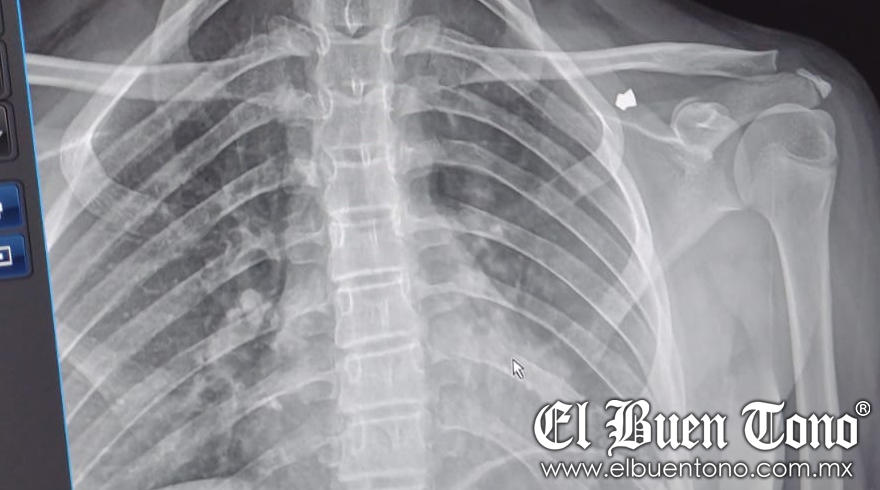

Córdoba, Ver.- Una menor de 11 años de edad, fue lesionada en la espalda por un sujeto hasta el momento desconocido que accionó una arma de diabolos. La agresión se registró la tarde del lunes en la avenida 5 entre calles 11 y 13, al momento que la menor, identificada como Skarlet de Jesús “N”, caminaba por esa dirección en donde se ubican algunos comercios.

De momento fue lesionada en la parte trasera del hombro del lado izquierdo. Familiares piden la intervención de las autoridades correspondientes para que en dicho lugar se instalen cámaras de vigilancia, ya que alguna otra persona podría ser agredida.